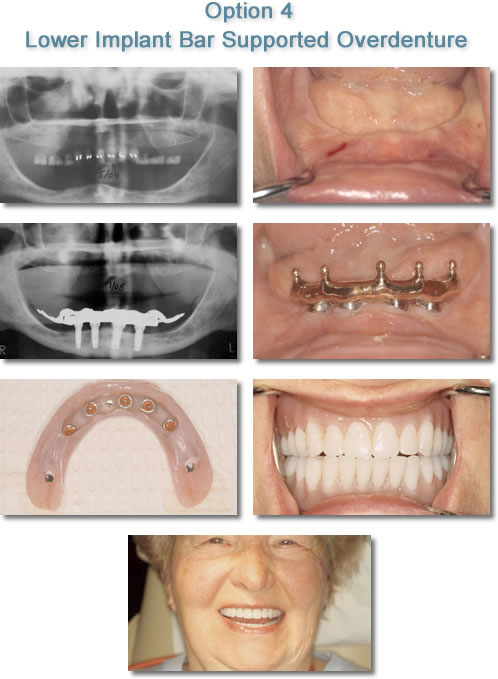

Removable Implant Supported Overdenture

Option 4: Removable Implant Supported Overdenture This type of prosthesis supported by implants has been the most common means of replacing an entire arch of teeth. This prosthesis resembles a conventional removable denture but does not rest on the patient's gum tissue. This prosthesis rests completely on the implants and is held securely in place by a variety of attachments.

The Removable Implant Supported Overdenture is a great option for a patient missing all of their teeth in the upper or lower jaw because it is more affordable than the Fixed Options and because it is more comfortable than a conventional denture.

The advantages of a Removable Implant Supported Overdenture over a conventional denture are numerous.

- In the upper jaw, the prosthesis does not cover the roof of the mouth.

- The prosthesis does not move and cause sore spots.

- The implant supported prosthesis stops the loss of bone that occurs with a conventional denture.

- The prosthesis restores facial dimensions and lip support that have been lost. In other words it reverses the Aging Process of Conventional Dentures.

The various attachments used to secure the Removable Implant Supported Overdenture to the implants are discussed with the patient at the Consultation Appointment.